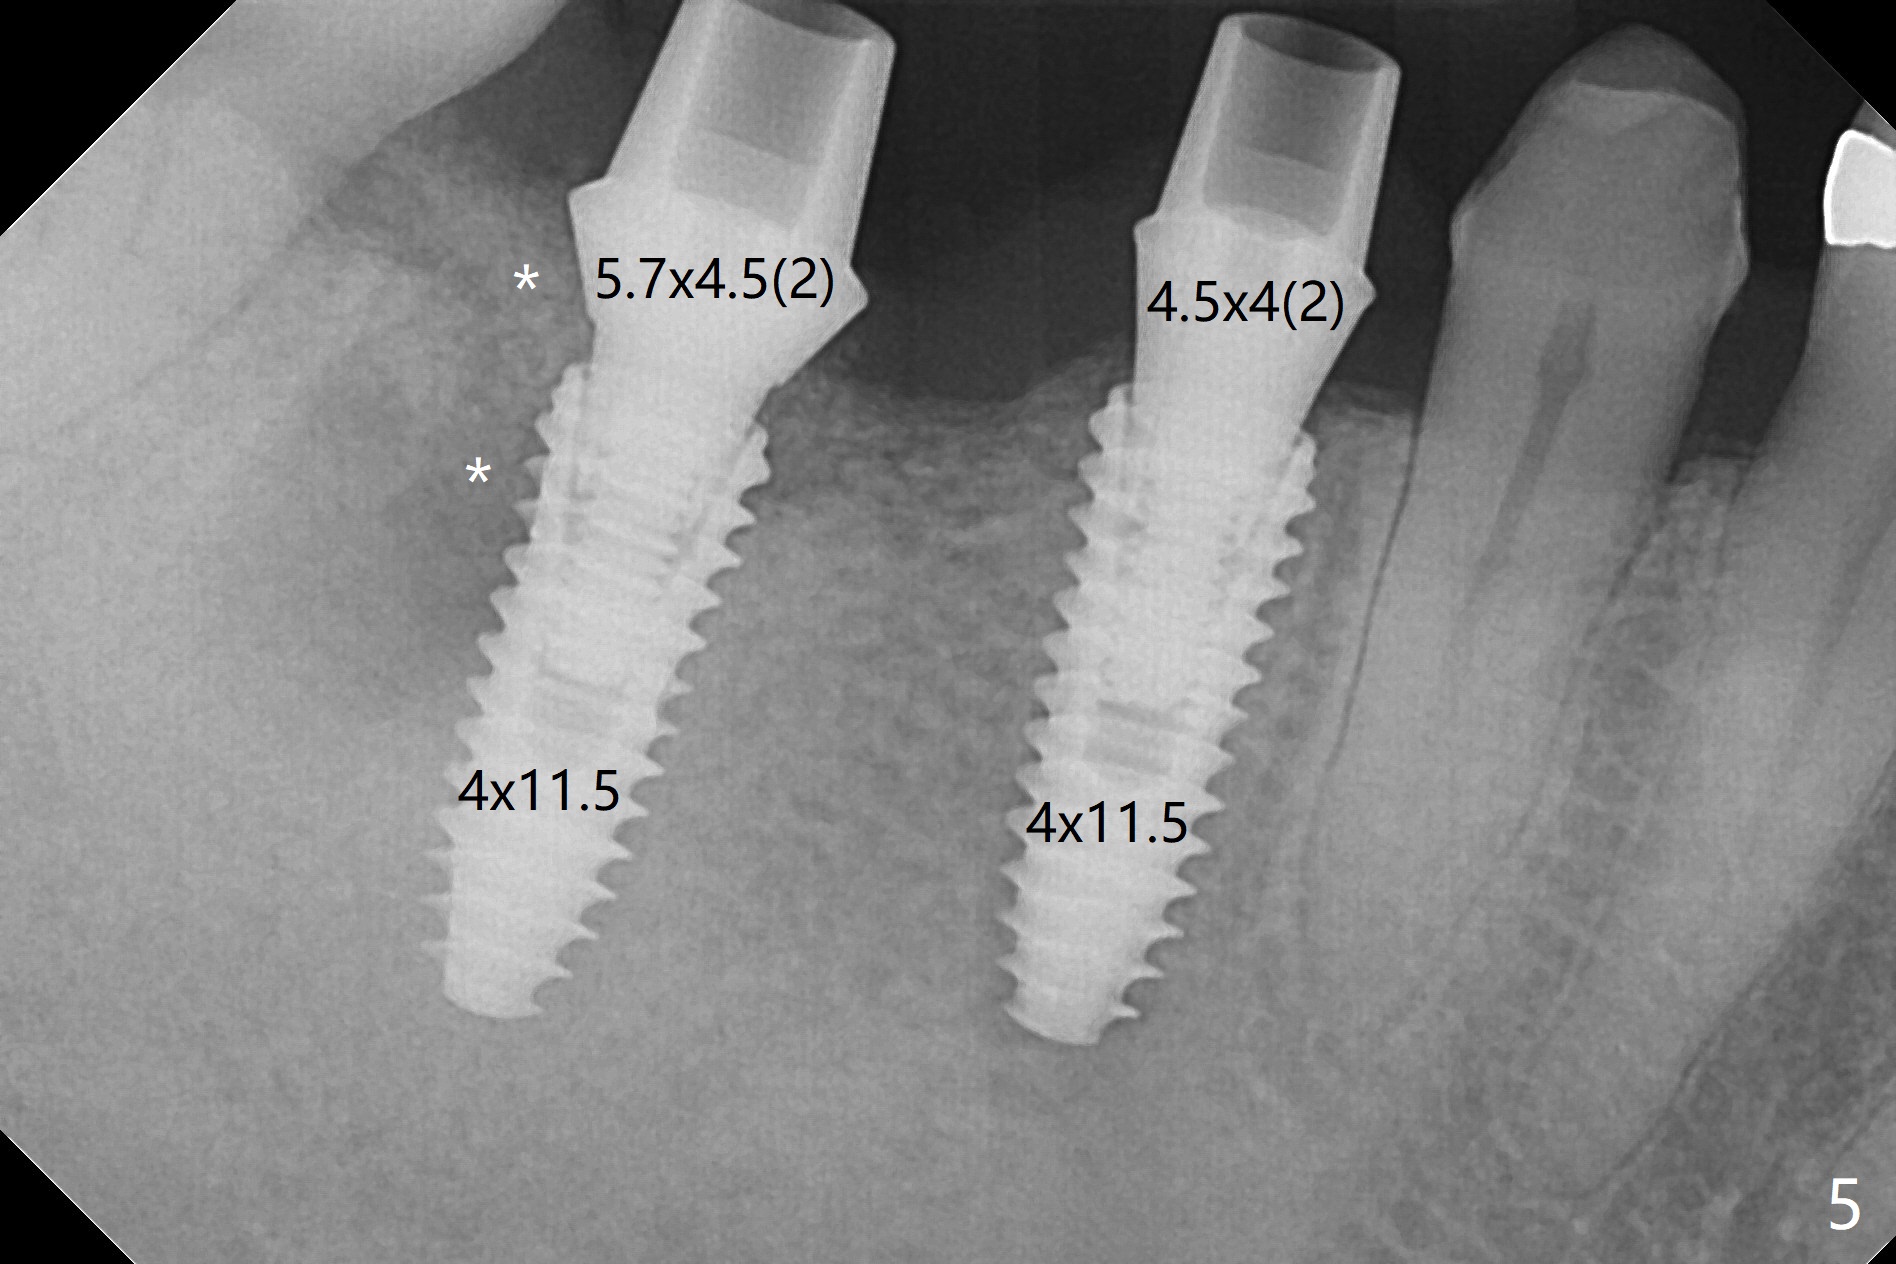

The edentulous area at #30 looks narrow after #31 extraction (Fig.1) and after incision (Fig.2). As planned, osteotomy is established at #30 as a premolar and at the mesial slope of #31 socket (Fig.3). Following adjustment of the trajectory at #30 and sequential osteotomy until 3.5x11.5 mm, two of 4x10 mm dummy implants are inserted with stability as well as dummy abutments (Fig.4). Final implants are 4x11.5 mm with insertion torque > 50 Ncm; after suturing, abutment margins are subgingival, particularly at #31 (Fig.5 (*: Vera Graft)). Periodontal dressing is applied. Provisional will be fabricated when the wound heals. It appears that the small and regular implants are appropriate for the narrow mesiodistal space at #30 and 31. There appears to be bone growth around the implants nearly 4 months postop (Fig.6).